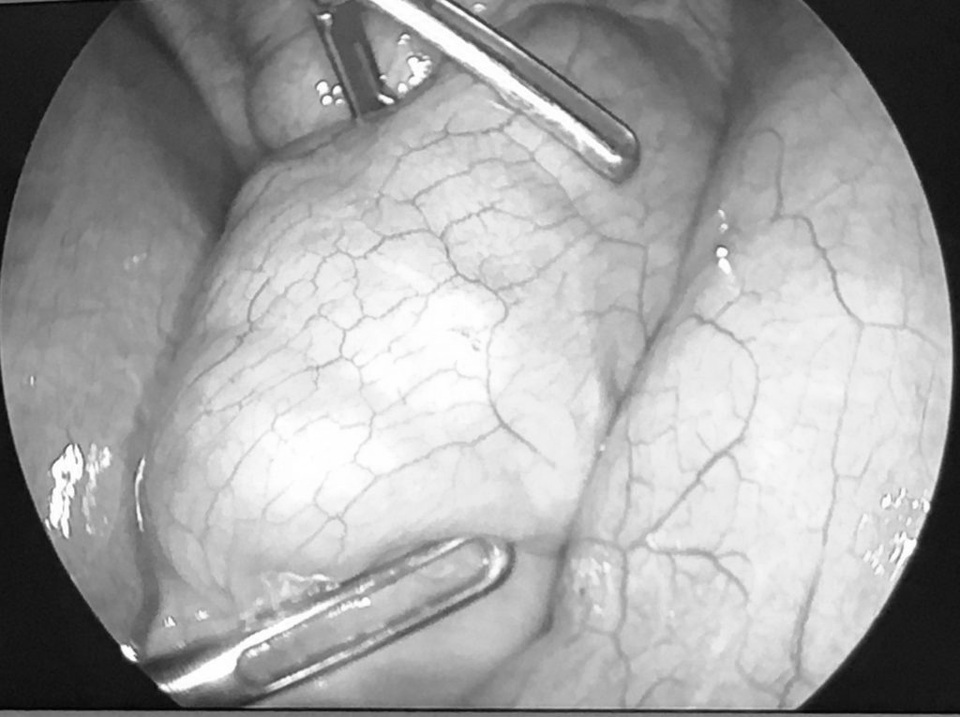

Điều bất ngờ là trong quá trình nội soi ổ bụng, bác sĩ phát hiện suốt hơn 1 mét hỗng-hồi tràng của trẻ lấp đầy những khối bã lớn dai chắc.

Các khối bã gây tắc ruột này được kết cấu từ những bó sợi dai màu nâu đỏ tương tự như thịt bò, nai khô hoặc các loại que cay…được bày bán tràn lan trước các cổng trường.

Sau 3 ngày điều trị nội khoa không thể cải thiện được tình trạng tắc ruột, cháu bé được chỉ định phẫu thuật. Ca mổ lấy bã thức ăn, sau đó, được thực hiện thành công. Hiện tại, thể trạng của bệnh nhi khá tốt và sắp được ra viện.